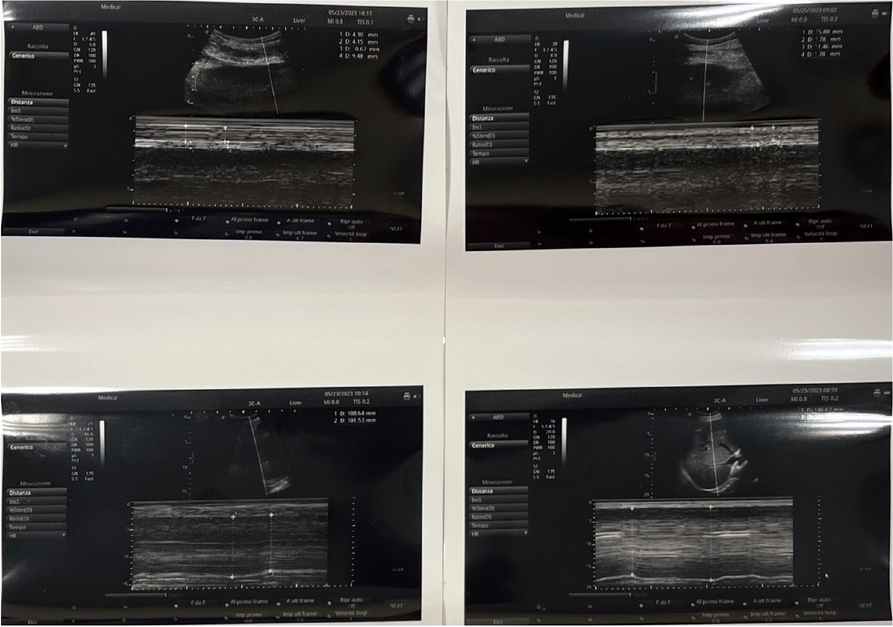

Patient 1

Patient 2